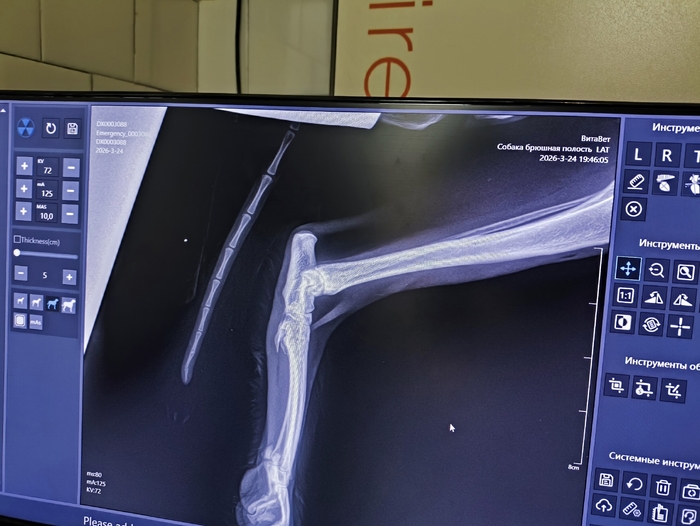

Кот был отловлен и отвезён в клинику, где на ренгене увидели старый перелом , который сросся неправильно, но жить ему не мешает, удалили три последних зуба и обработали ту самую рану - дырку без кожи.